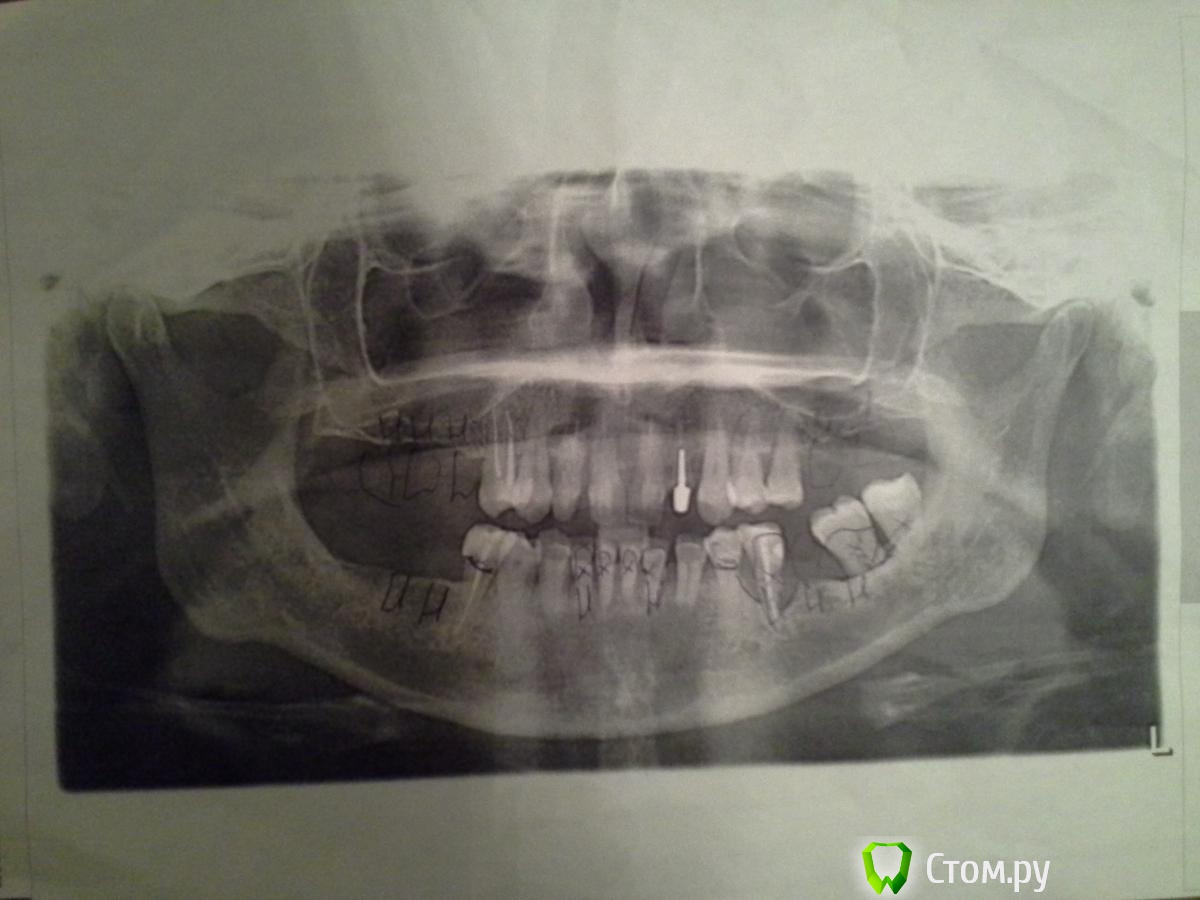

diesel87 Опубликовано 6 декабря, 2013 Поделиться Опубликовано 6 декабря, 2013 Добрый вечер, нужен снимок панорамный для оценки пародонта. 1 Ссылка на комментарий

Rayskaya Опубликовано 6 декабря, 2013 Автор Поделиться Опубликовано 6 декабря, 2013 Снимок во вложении Ссылка на комментарий

pawa Опубликовано 6 декабря, 2013 Поделиться Опубликовано 6 декабря, 2013 (изменено) Добрый день, прошу совета в такой ситуации: планируется установка нескольких имплантов, Хм... несколько это 2-3, ну 4-5, у вас я на снимке увидел 11 и еще 2 синуслифтинга и тд. При таком количестве имплантатов надо подумать, а есть ли смысл оставлять во рту остатки своих зубов или протезироваться только с опрой на имплантаты? Изменено 6 декабря, 2013 пользователем pawa 1 Ссылка на комментарий

Rayskaya Опубликовано 6 декабря, 2013 Автор Поделиться Опубликовано 6 декабря, 2013 С количеством имплантов еще не определились, схематично условно показаны, интересно Ваше мнение- возможно ли более рациональное решение по количеству необходимых имплантов? Имеющиеся зубы хотелось бы оставить, и по вопросу чистки карманов- какое Ваше мнение? Ссылка на комментарий